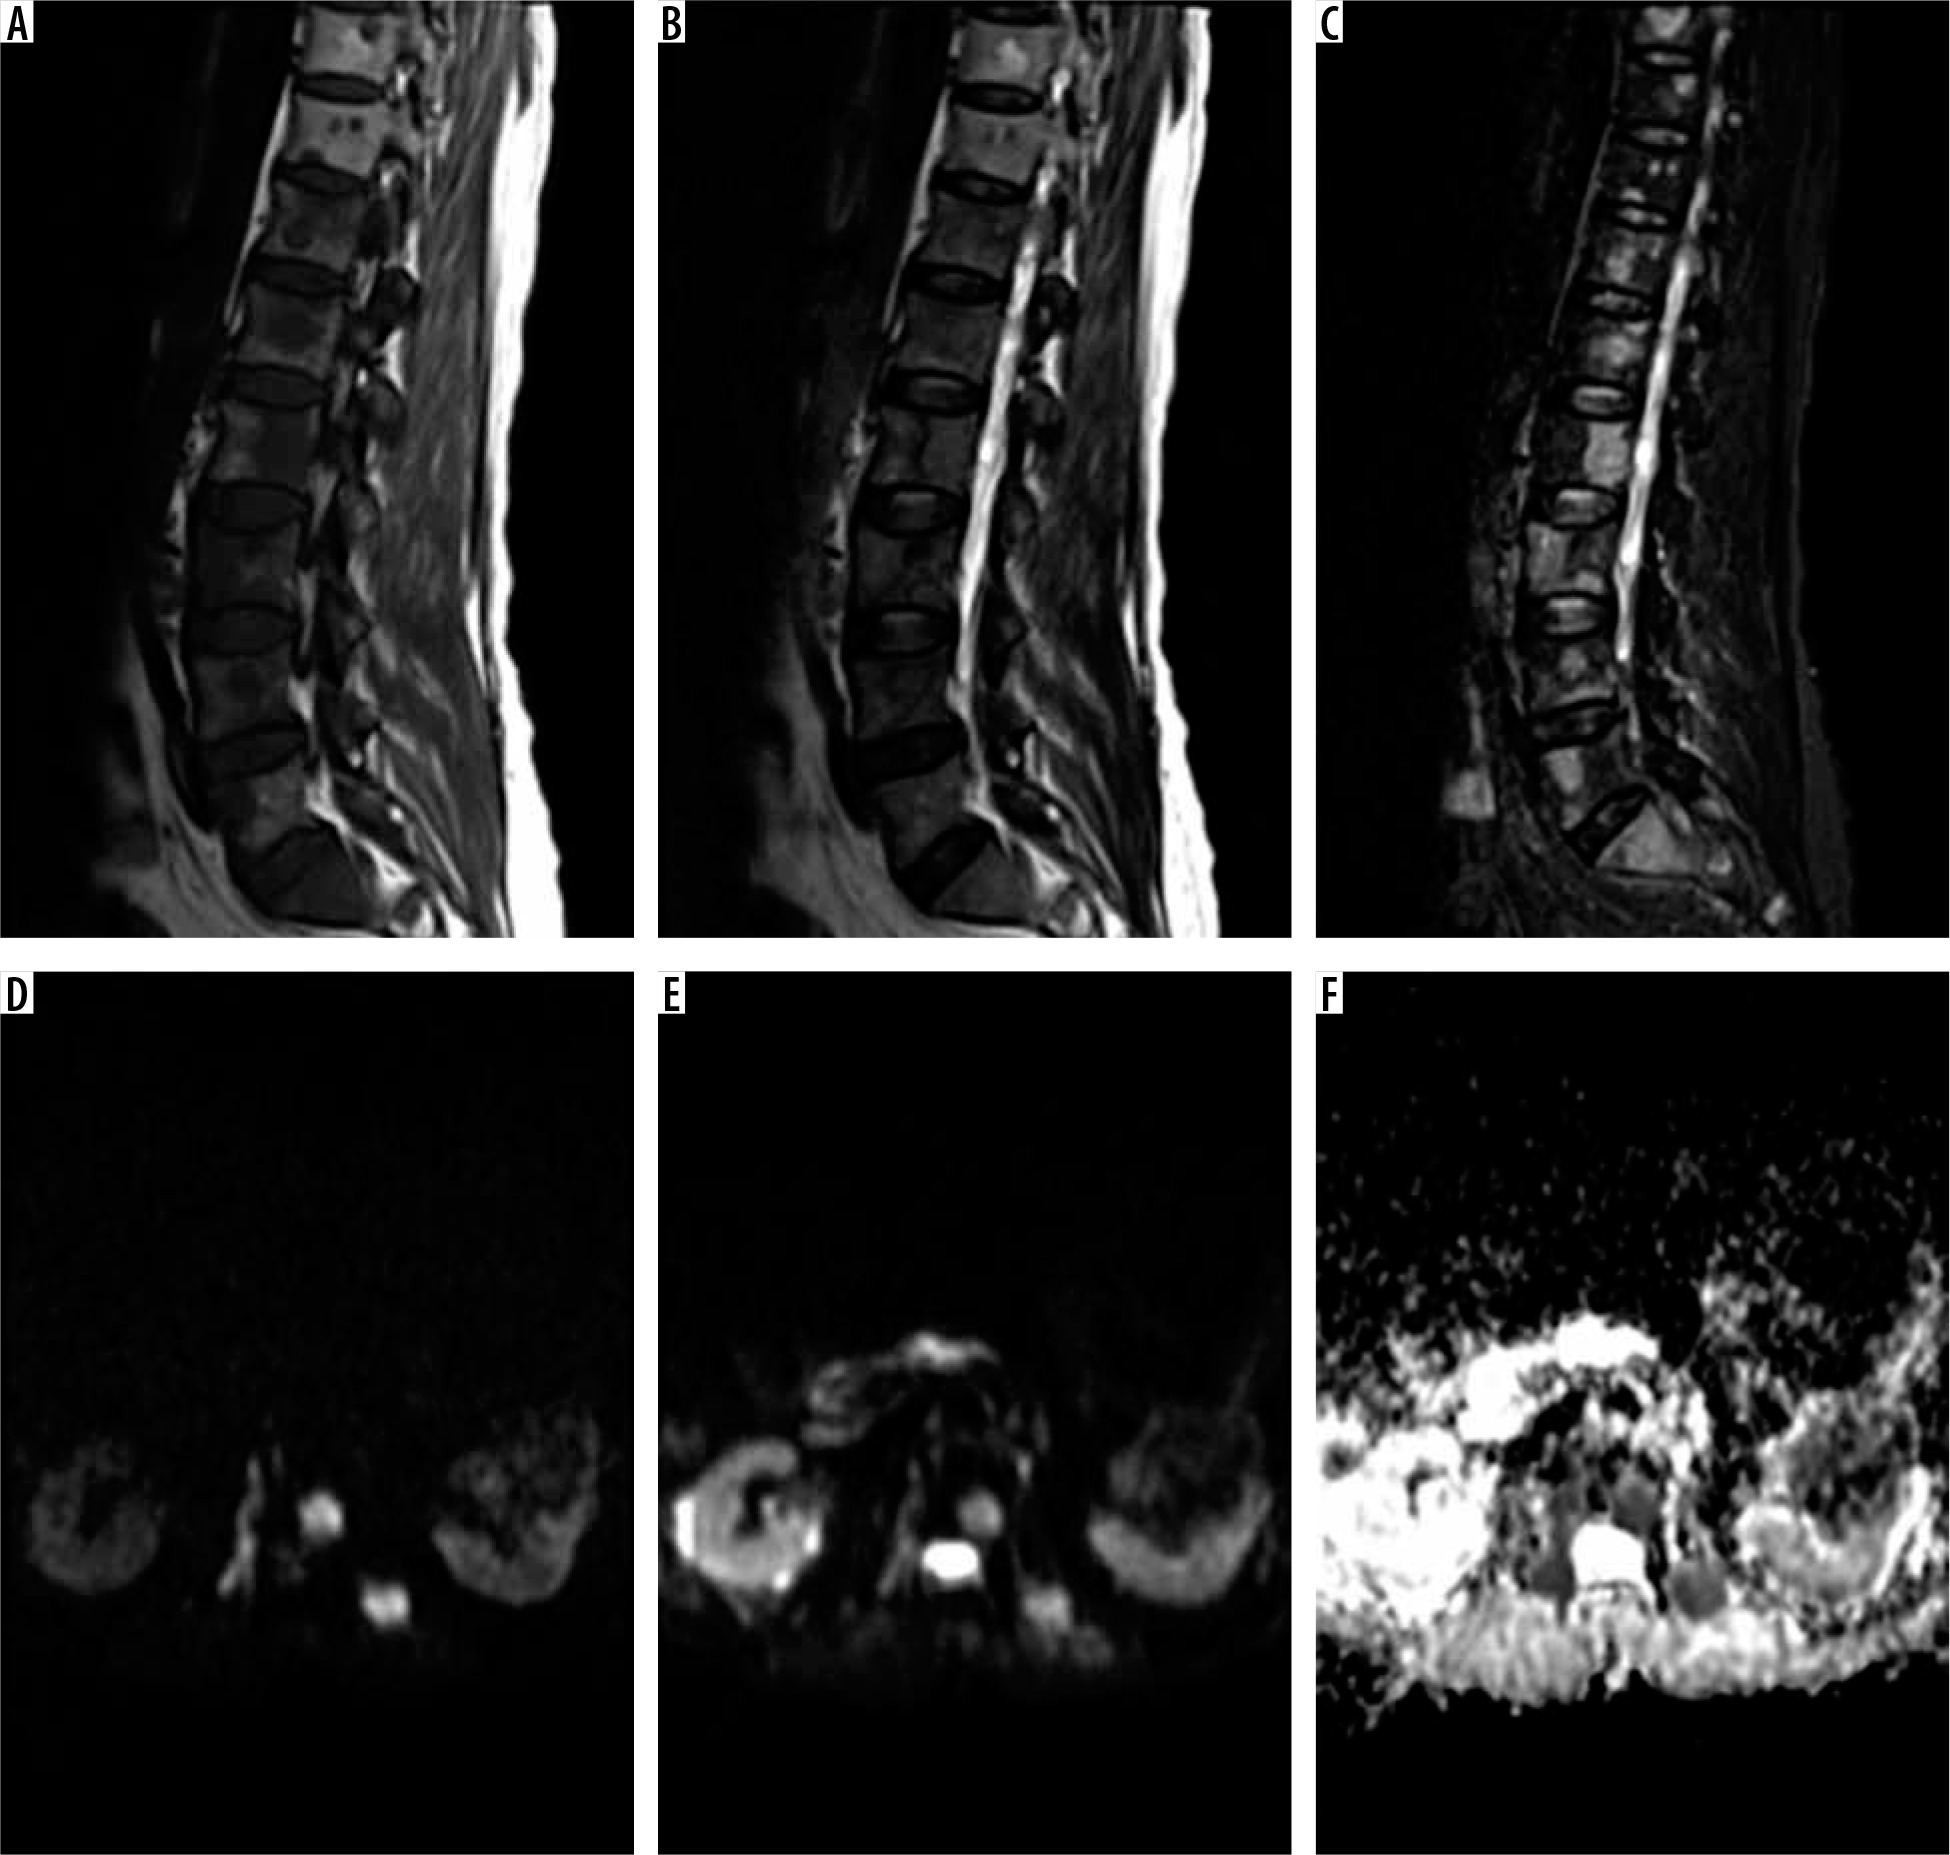

Figure 1

Atypical haemangioma in a 69-year-old woman. A) The characteristic polka-dot sign. B-C) The T1 and T2 sequences, respectively. The haemangioma is hypointense in T1- and hyperintense in T2-weighted images. D-F) Diffusion-weighted imaging in b values of 50, 400, and the apparent diffusion coefficient (ADC) map. The ADC of the lesion equals 1892 × 10-6 mm2/s